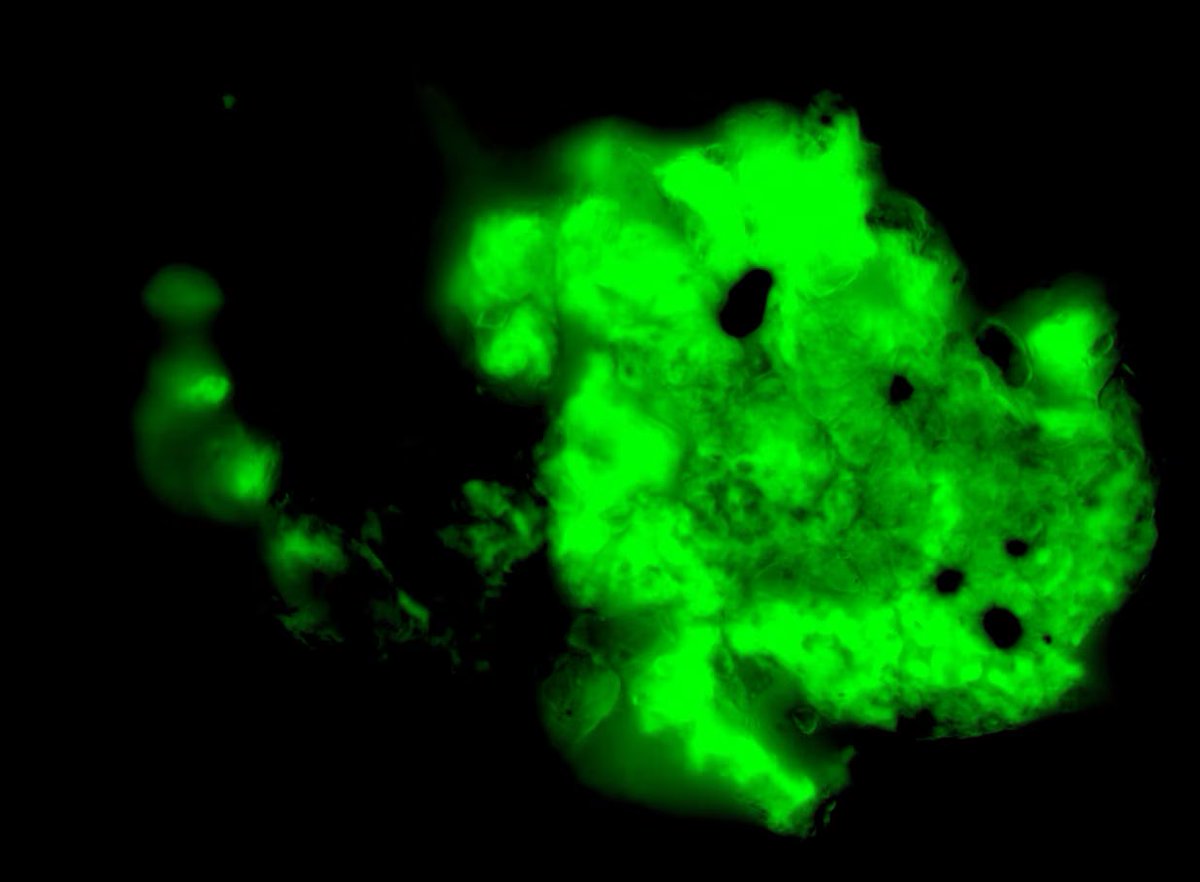

Seit mehr als zwei Jahren versuchen Wissenschaftler zu verstehen, warum Millionen von Menschen auf der ganzen Welt trotz Genesung von ihrer akuten COVID-19-Infektion unter anhaltenden Symptomen leiden. Sie haben mehrere Hypothesen aufgestellt, darunter das Vorhandensein von

Mikroklumpen - winzigen Blutgerinnseln, die Kapillaren verstopfen und möglicherweise den Blut- und Sauerstofffluss beeinträchtigen können. In einer Studie aus dem Jahr 2021 wiesen die Physiologin Etheresia Pretorius von der Universität Stellenbosch in Südafrika und ihre Kollegen

als erste darauf hin, dass Mikroklumpen mit diesem schwächenden Zustand, der als Long COVID bezeichnet wird, zusammenhängen könnten. In einer Folgestudie wiesen sie und ihre Kollegen nach, dass das SARS-CoV-2-Spike-Protein die Bildung solcher Gerinnsel auslöst, die der

körpereigene Prozess zur Auflösung von Blutgerinnseln nicht ohne weiteres aufzulösen scheint. Diese Erkenntnis hat einige Wissenschaftler in den Vereinigten Staaten dazu veranlasst, unter Anleitung von Pretorius Menschen mit Long COVID auf Mikroklumpen zu testen.

David Putrino, ein Wissenschaftler für Rehabilitation und Long COVID am Mount Sinai Health System, und seine Mitarbeiter sammeln Blutproben, um nach Mikroklumpen zu suchen. "Wir sind noch ganz am Anfang", sagt Putrino. "Wir haben bisher nur ein paar Dutzend Leute getestet." Aber

jede Probe von Patienten, die an Long COVID erkrankt sind hat solche Gerinnsel gezeigt. Im Moment sehen Putrino und sein Team einen Zusammenhang zwischen der Anzahl der Mikroklumpen auf einem Objektträger und dem Schweregrad der kognitiven Beeinträchtigung eines Patienten. Dazu

gehört die Fähigkeit, Emotionen zu regulieren, langfristige Lösungen für Probleme zu planen und zu erarbeiten oder Wege zu finden, mit sich verändernden Situationen in Echtzeit umzugehen. Das Forschungsteam entwickelt auch ein objektives Maß für Mikroklumpen. "Wir befinden uns

noch in einem sehr rudimentären Stadium", sagt Putrino. Einige Experten halten die Hypothese der Mikroklumpen zwar für plausibel, glauben aber, dass sie nur ein Teil des Puzzles von Long COVID sein könnte. Sie wünschen sich jedoch weitere Untersuchungen, die zeigen, wie diese

Gerinnsel zu den Symptomen von Long COVID beitragen und ob ihre Beseitigung zu besseren gesundheitlichen Ergebnissen führt. Wenn diese Mikroklumpen über längere Zeit bestehen bleiben, könnte der Körper Autoantikörper produzieren - Proteine, die unbeabsichtigt körpereigenes

gesundes Gewebe angreifen und zu schwächenden Störungen führen. "Es sind diese Menschen, um die wir uns besonders sorgen", sagt Etheresia Pretorius.